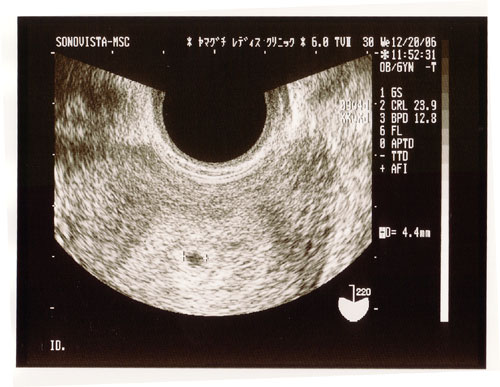

5 産科一般超音波検査 初期編 正常所見4 7週 日本産婦人科医会

妊娠2ヶ月 妊娠4週 5週 6週 7週 妊娠初期 の超音波写真 妊娠 出産 育児に関する総合情報サイト ベビカム

妊娠4週目 4w0d 6d のエコー写真とエピソード 妊娠2ヶ月 Cozre コズレ 子育てマガジン

妊娠4週目のエコー写真 胎芽や胎嚢 初期症状や流産のこと 妊娠初期 All About

妊娠4週0日 4w0d の超音波 エコー 写真

妊娠2ヶ月 妊娠4週 5週 6週 7週 妊娠初期 の超音波写真 妊娠 出産 育児に関する総合情報サイト ベビカム

5 産科一般超音波検査 初期編 正常所見4 7週 日本産婦人科医会

妊娠4週3日 4w3d の超音波 エコー 写真

妊娠4週4日 4w4d の超音波 エコー 写真

妊娠4週 赤ちゃんのエコー写真 超音波写真まとめ たまひよ